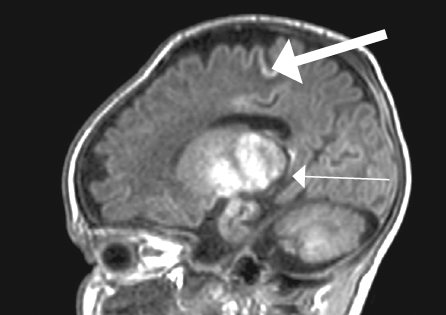

Рис. 1. Магнитно-резонансная томограмма головного мозга пациента, фронтальный срез: а— на уровне базальных ганглиев; b— с визуализацией гиппокампов / Fig. 1. Patients brain, magnetic resonance imaging, front: a – T1 hyperintensity symmetric of basal nuclei; b–hippocampus, cortex and brain hypotrophy are evidence

На 27-й день жизни выполнена МРТ головного мозга, диагностирована гипоксически-ишемическая энцефалопатия с двухсторонним поражением базальных ядер, ножек мозга, прецентральной извилины и гиппокампов. Кроме того, выявлена смешанная гидроцефалия по заместительному типу (рис. 1, 2). Визуализируется симметричное усиление МР-сигнала в области базальных ганглиев (рис. 1, а), гиппокампов (рис. 1, b), также определяется значительное расширение субарахноидальных пространств, преимущественно над лобными, височными долями больших полушарий с расширением сильвиевой щели, расширение борозд и истончение коры больших полушарий (наружная гидроцефалия по заместительному типу), расширение передних отделов боковых желудочков.